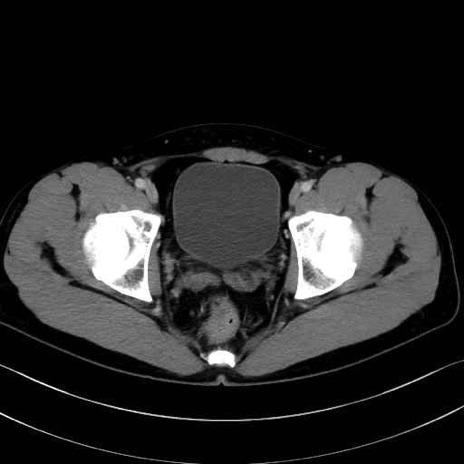

2. 腸腰筋群と骨盤底筋

大腰筋 (Psoas major)

腸骨筋 (Iliacus)

肛門挙筋 (Levator ani)